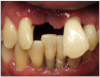

Patient presents with maxillary and mandibular anterior teeth having been extracted and is wearing transitional removable appliances.

Decisions need to be made as to smoking cessation, periodontal treatment and tooth replacement. The photos and dental radiographs were taken prior to the referral (Figure 23 through Figure 25), and the periodontal charting done post-op (Figure 26).

Figure 23.

Figure 23

Figure 24.

Figure 25.

Figure 25